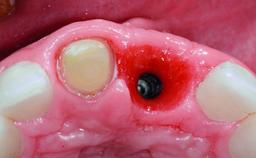

Replacement of a Missing Upper Left Central Incisor: Late Placement of an RC Bone Level Implant, CAD/CAM Zirconia Abutment

A healthy 37-year-old female patient was referred for a consultation on the replacement of missing tooth 21 with an implant-supported restoration. She stated that several years previously the tooth had been traumatically avulsed following a motor vehicle accident. The tooth was replaced with a three-unit fixed partial denture (FPD) immediately afterwards. Over time, she became disillusioned with the FPD and looked for a different option, including orthodontic therapy. She presented still in her orthodontic appliances, with the pontic sectioned free from the FPD but attached to the archwire. Her orthodontist felt that orthodontic treatment had been successfully completed, but nevertheless referred her before removing the appliances in case adjustments were necessary.